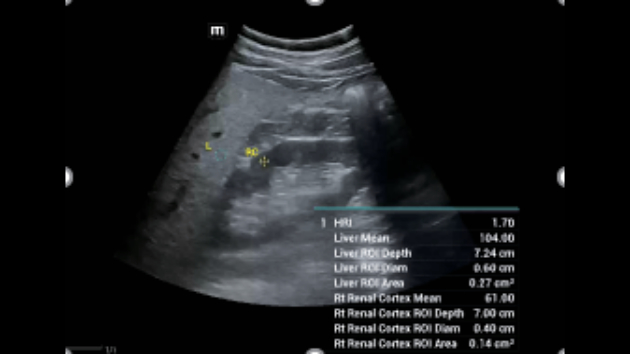

Soluzioni di diagnostica per immagini complete con tecnologia ZST+

La piattaforma ZST+ è un'innovazione straordinaria, che rappresenta un'evoluzione nel campo dell'ecografia. Grazie alla trasformazione delle metriche a ultrasuoni dal beamforming convenzionale all'elaborazione basata sui dati di canale, supera la tradizionale limitazione del trade-off tra risoluzione spaziale, risoluzione temporale e uniformità dei tessuti, offrendo una qualità d'immagine eccezionale per infinite soluzioni di imaging con miglioramenti continui.